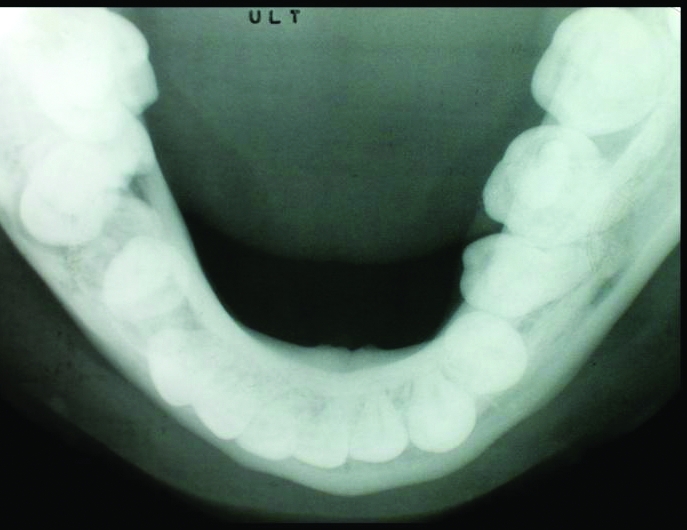

Figure 3.

Occlusal radiography of the patient.

Subsequent radiographic examination revealed an ankylosed second primary molar which caused impaction of the second premolar and tipping of the first molar. The second premolar which had a dilacerated root failed to erupt and was lying close to the lower border of the mandible (Figures 2 and 3). The tooth appeared to be in close proximity to the inferior alveolar canal as clearly seen in panoramic radiograph (Figure 2).